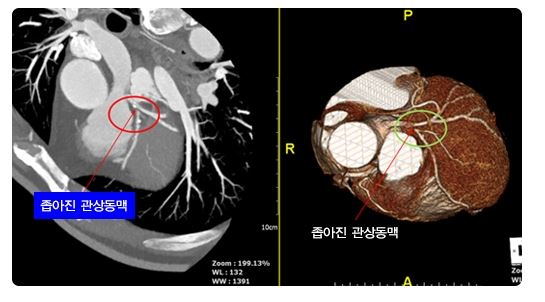

3) 심장 컴퓨터 단층 촬영(Computed Tomography, CT) 검사

최근 심장 CT의 발전으로 비침습적이고 비용-효과적이며 높은 정확도를 가진다는 장점이 있습니다. 흉통을 호소하는 환자에서 안정 관상 동맥 질환의 진단을 위한 첫 도구로 심장 CT를 시행하기도 합니다.